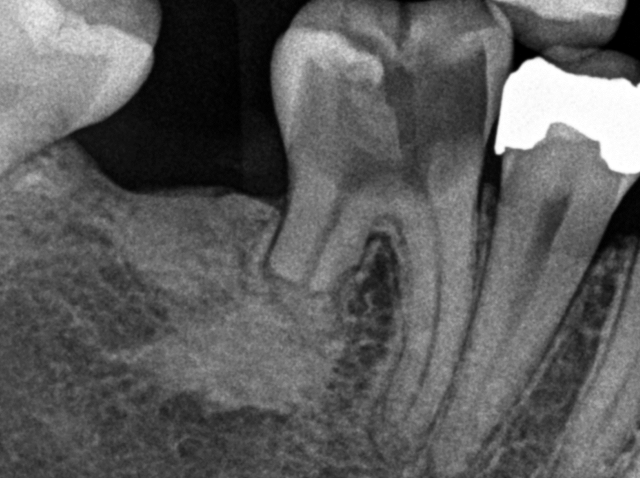

What is seen in these radiographs?

Cementoblastoma